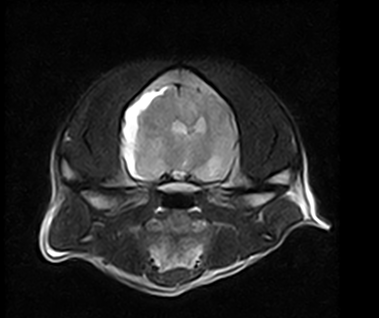

脳出血(硬膜下出血)MRI

上記症例と同一